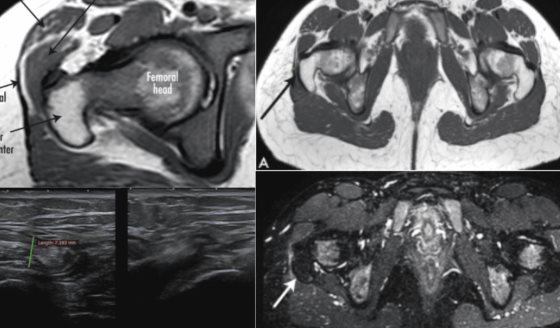

La neumonía es una infección que inflama los sacos de aire en uno o ambos pulmones. Estos sacos pueden llenarse de líquido o pus, causando síntomas como tos con flema, fiebre, escalofríos y dificultad para respirar.

Puede ser provocada por bacterias, virus o hongos y su gravedad varía desde casos leves hasta potencialmente mortales.

La neumonía puede afectar a cualquier persona, pero es más peligrosa en bebés y adultos mayores de 65 años o en personas con enfermedades crónicas o sistemas inmunológicos debilitados.

En algunos casos, la neumonía puede causar problemas graves, como:

· Bacteriemia: Las bacterias pueden pasar a la sangre y afectar otros órganos.

· Dificultad para respirar: Puede ser necesario usar un respirador en casos graves.

· Derrame pleural: Acumulación de líquido alrededor de los pulmones que puede requerir drenaje.

· Absceso pulmonar: Formación de pus en los pulmones, que a veces necesita tratamiento con cirugía o drenaje.